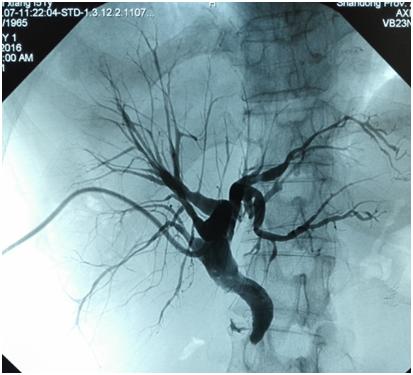

胆道穿刺置管成功后DSA造影

胆汁引流体外后(PTCD术后),患者的黄疸立刻得到缓解,每天要引流出大约 600ml的胆汁,约2 ~ 4周的时间患者的黄疸就会消退,食欲、体质等一般状况会得到明显的改善,等黄疸消退后还需正规抗肿瘤治疗,效果会更好,患者的生存时间会大大延长。

胆道穿刺外引流管